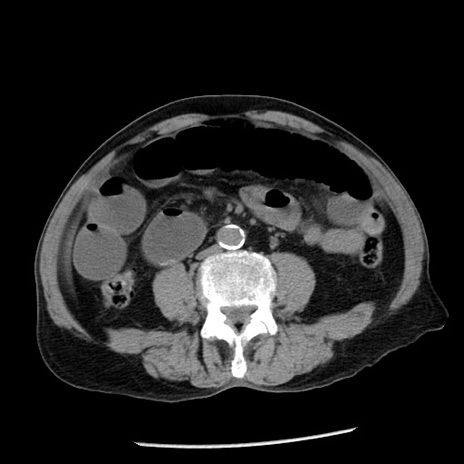

症例26(横断像)

【症例】80歳代男性

【主訴】嘔吐

【現病歴】昨晩2回嘔吐あり、今朝になっても嘔吐あり。来院。

【既往歴】胃潰瘍

【身体所見】意識清明、BT 37.6℃、BP 166/95mmHg、HR 100bpm、SpO2 97%、腹部:平坦・軟、腸蠕動音聴取良好、圧痛なし。

【データ】WBC 21900、CRP 1.46